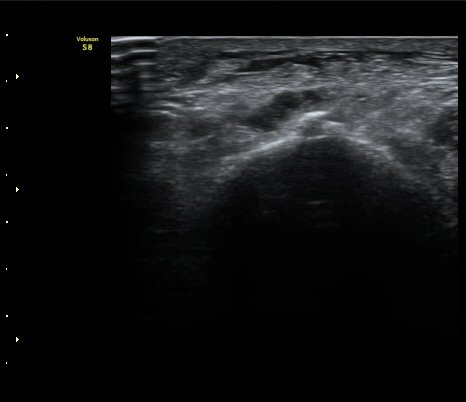

Àδë Á¾°ñºÎÂøºÎ Á¾´Ü¸é°Ë»ç¿Í Ⱦ´Ü¸é°Ë»ç¿¡¼­ Á¾°ñÀÇ °ß¿­°ñÀýÀÌ °üÂ÷µÊ(»çÁø 4, 5).